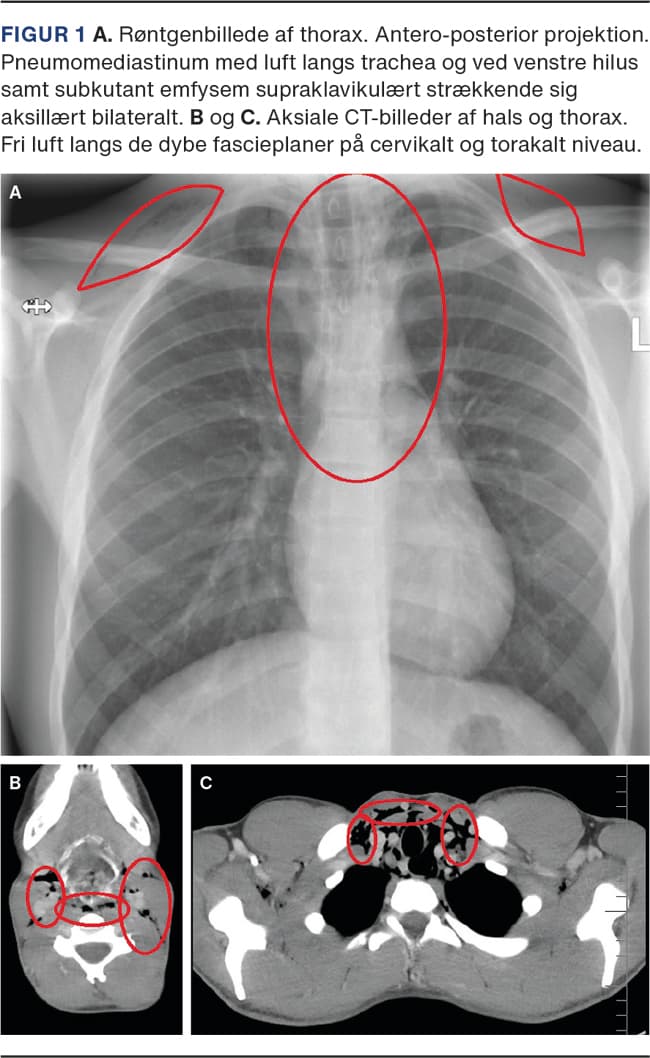

Den objektive undersøgelse inklusive fiberlaryngoskopi viste kun emfysem på halsen og fravær af Hammans tegn. De vitale værdier var alle i normalområdet. Røntgen af thorax viste pneumomediastinum med fri luft langs trachea og venstre hilus samt subkutant emfysem supraklavikulært strækkende sig aksillært bilateralt (Figur 1).

På mistanke om perforation af øsofagus eller trachea blev der foretaget CT af thorax. Der sås pneumomediastinum og emfysem på halsen, men ingen perforation eller anden ætiologisk forklaring. Patienten blev henvist til pædiatrisk vurdering, hvor man pga. spontan bedring i tilstanden og god almentilstand vurderede, at patienten kunne følges ambulant med kontrol en uge efter. Ved denne kontrol var patienten symptomfri, og en kontrolrøntgenundersøgelse af thorax viste normale forhold. Der har ikke været recidiv af symptomer eller objektive fund siden.